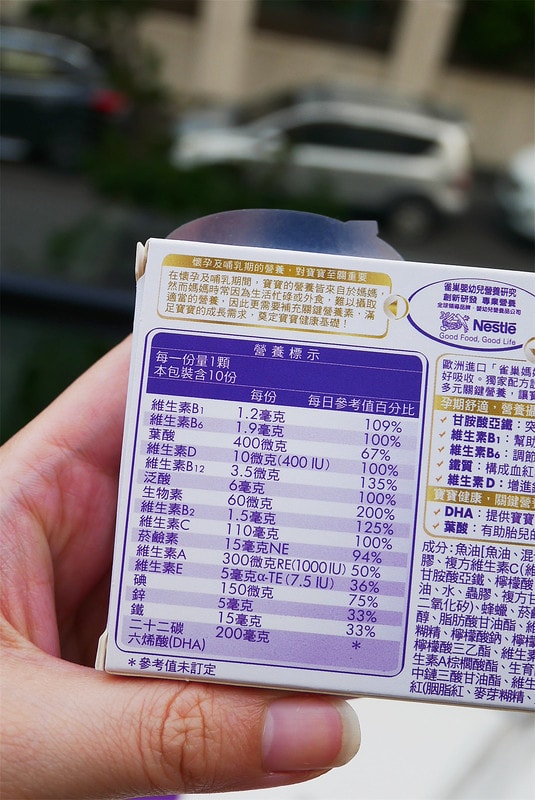

雀巢媽媽膠囊體驗組長這樣

一盒裏頭有十顆

左上角寫的MADE IN ITALY

我才知道原來是義大利來的呀!

營養標示包裝上都寫得很清楚喔

比方說孕期最需要的鐵、DHA、葉酸、綜合維生素等

裏頭都有包含到唷

一顆裡面有葉酸、B群等綜合維他命、足量DHA、甘胺酸亞鐵等孕期關鍵營養,

甘胺酸亞鐵的突破性科技,更可以輕鬆幫助鐵質攝取

可滿足各階段關鍵營養需求,適合備孕、懷孕初、中、晚期以及哺餵母乳的媽媽。”